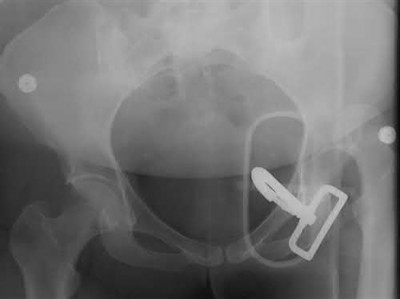

A 76-year-old male community ambulatory presented to clinic complaining of pain in the left groin that has been persistent for the last 8 months. Radiographs obtained from clinic are seen in Figure A. You suspect a femoral neck nonunion and obtain a CT scan which confirmed it. Which of the following statements is true?

A total hip arthroplasty (THA) after nonunion of a femoral neck fracture would provide the best long term outcomes in a 76-year-old male who is a community ambulator.

After nonunion of a femoral neck fracture, hemiarthroplasty and THA are good salvage option for the physiologically older patients. When deciding between these two options, THA is better for active and cognitively intact patients. THA is also indicated in patients with radiographic evidence of degenerative disease about the acetabulum. Hemiarthroplasty is advocated for patients who are older and less active.

Yang et al. retrospectively investigated the risk factors for nonunion in patients treated with cannulated screws. They reviewed 202 patients who had femoral neck fractures and were treated with internal fixation with cannulated screws. They identified that triangle configuration, displaced fracture, borderline or unacceptable reduction, and increased screw shaft subchondral purchase over the femoral neck were all risk factors for nonunion after internal fixation.

Inverted triangle configuration was found to increase rate of union.

Archibeck et al. retrospectively reviewed the outcomes of 102 THAs after failed internal fixation for a hip fracture (including both femoral neck and intertrochanteric). They concluded that the conversion of failed hip internal fixation has elevated risks compared to a primary THA, however, it may still be successful. The biggest concern for these patients postoperatively are periprosthetic fracture and dislocation.

Figures and Illustrations:

Figure A is an AP pelvic radiograph demonstrating a nonunion of a femoral neck fracture after suboptimal fixation with 3 cannulated screws in a triangle configuration.

Illustration A is an AP radiograph of the left hip in this patient following conversion to THA.

Illustration B is a radiograph demonstrating a valgus osteotomy. Illustration C shows an example of a femoral neck nonunion with varus malreduction.

Incorrect Answers:

Answer 2: Varus reduction is closely correlated with failure in this fixation method.

Answer 3: The patient's best outcome would be with THA.

Answer 4: This would be a good option in a younger patient, but given age and functional capacity, the best option is THA.

Answer 5: Patients with hemiarthroplasty have lower rates of dislocation.